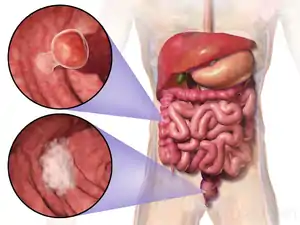

Traditional serrated adenoma is a precancerous type of bowel polyp.[1] There are usually no symptoms.[1]

It is typically found towards the end of the colon or rectum, when it appears on a stalk, or near the start of the colon, when it appears flat.[1]

Traditional serrated adenomas are a type of serrated polyp, and may occur sporadically or as a part of serrated polyposis syndrome. Traditional serrated adenomas are relatively rare, accounting for less than 1% of all colon polyps.[2][3] Usually, traditional serrated adenomas are found in the distal colon and are usually less than 10 mm in size.[2]